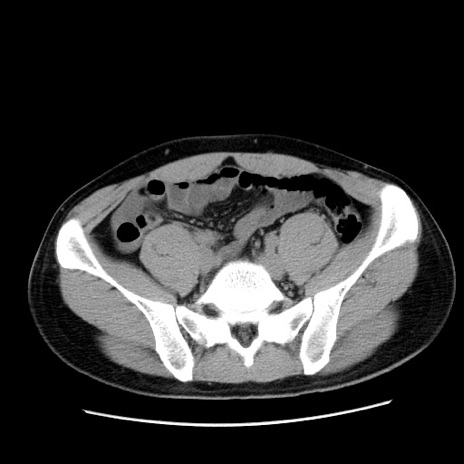

症例36(横断像)

【症例】20歳代 男性

【主訴】心窩部痛

【現病歴】今朝より上腹部痛あり。一旦軽快していたが再度出現したため救急要請。昨日夕に白身の魚を含む刺身を食べた。

【身体所見】BP 136/89mmHg、HR 74/min、BT 37.0℃、腹部:膨満、軟、心窩部に圧痛あり。反跳痛なし、筋性防御なし、腸雑音やや亢進あり。

【データ】WBC 17700、CRP 0.48